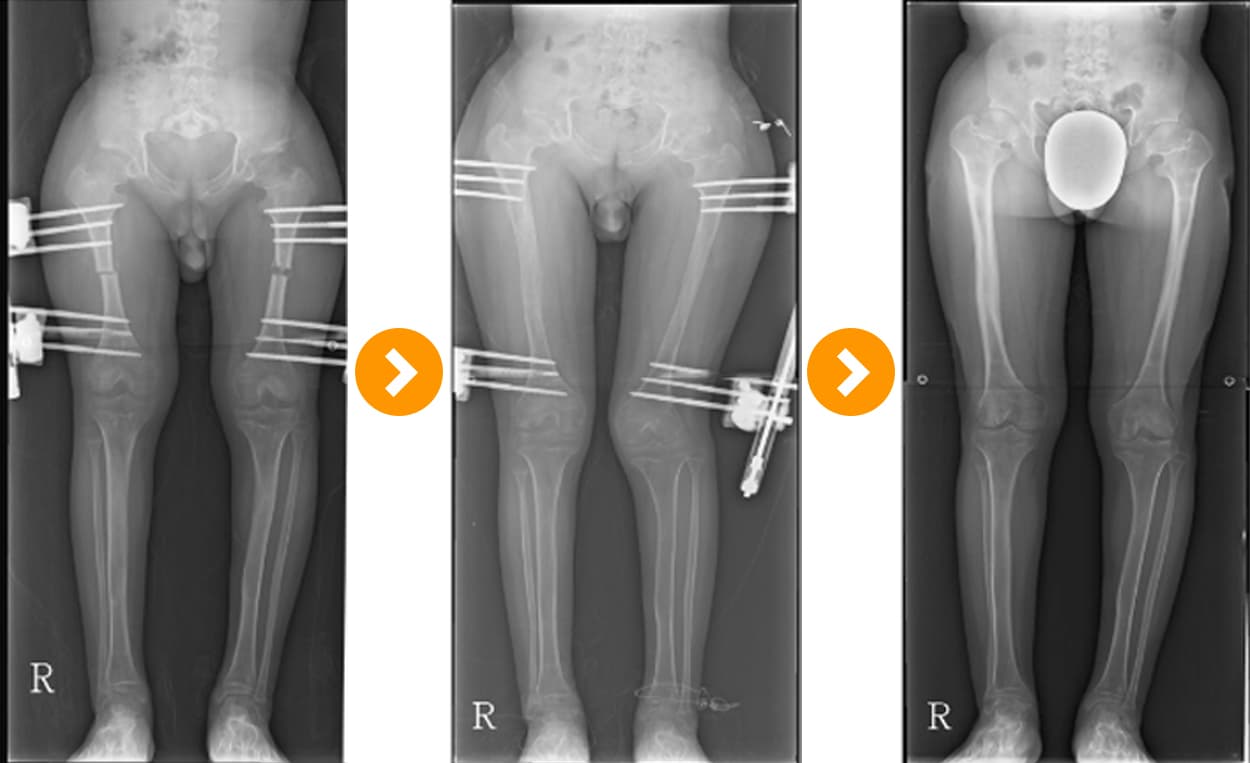

연골 무형성증경골연장술(8 cm) 및 대퇴골 연장술(8 cm)